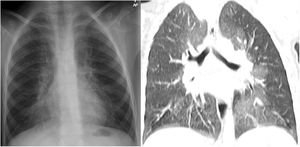

A 3-year-old pediatric patient was referred to our hospital with a history of recurrent respiratory infections and dry nocturnal cough following respiratory bronchiolitis at 5 months. On physical examination, she had mild tachypnea, subcostal and sternal retractions, and some bilateral crackling rales. A chest X-ray showed hyperinflation of both hemithoraxes and increased perihilar density (Fig. 1). Chest computed tomography (CT) scan was performed, showing areas of ground glass density in both lungs, more marked in the lingula and middle lobe (Figs. 1 and 2). An acute respiratory process was assumed, and symptomatic treatment with follow-up was prescribed. In the following months, several studies (autoimmunity, cystic fibrosis, pulmonary scintigraphy) were performed and found to be normal, and several drugs (mucolytics, β2 agonists, corticosteroids, and antibiotic therapy) were administered, but only partial symptomatic relief was achieved. A year later, a new CT was performed that showed persistence of lung findings, at which time the patient was diagnosed with neuroendocrine hyperplasia of infancy (NEHI).

Plain X-ray of the chest (A). Hyperinflation of both hemithoraxes and increased lung parenchyma density in the perihilar region. Chest CT, coronal reconstruction (B). Areas with a ground glass pattern affecting predominantly the middle lobe and the lingula, showing the typical distribution pattern of neuroendocrine hyperplasia of infancy.

NEHI is a type of interstitial lung disease that usually occurs before the age of 2, presenting with tachypnea, crackles, chest retractions, and hypoxemia1,2. The appearance on CT is characterized by a mosaic attenuation pattern with patchy areas and ground glass density affecting 4 or more lobes, typically the lingula and middle lobe. In certain cases, consistent clinical signs and functional tests may permit diagnosis of NEHI without the need for a lung biopsy1,2. The recommended treatment is supportive, with oxygen therapy and prevention measures2.